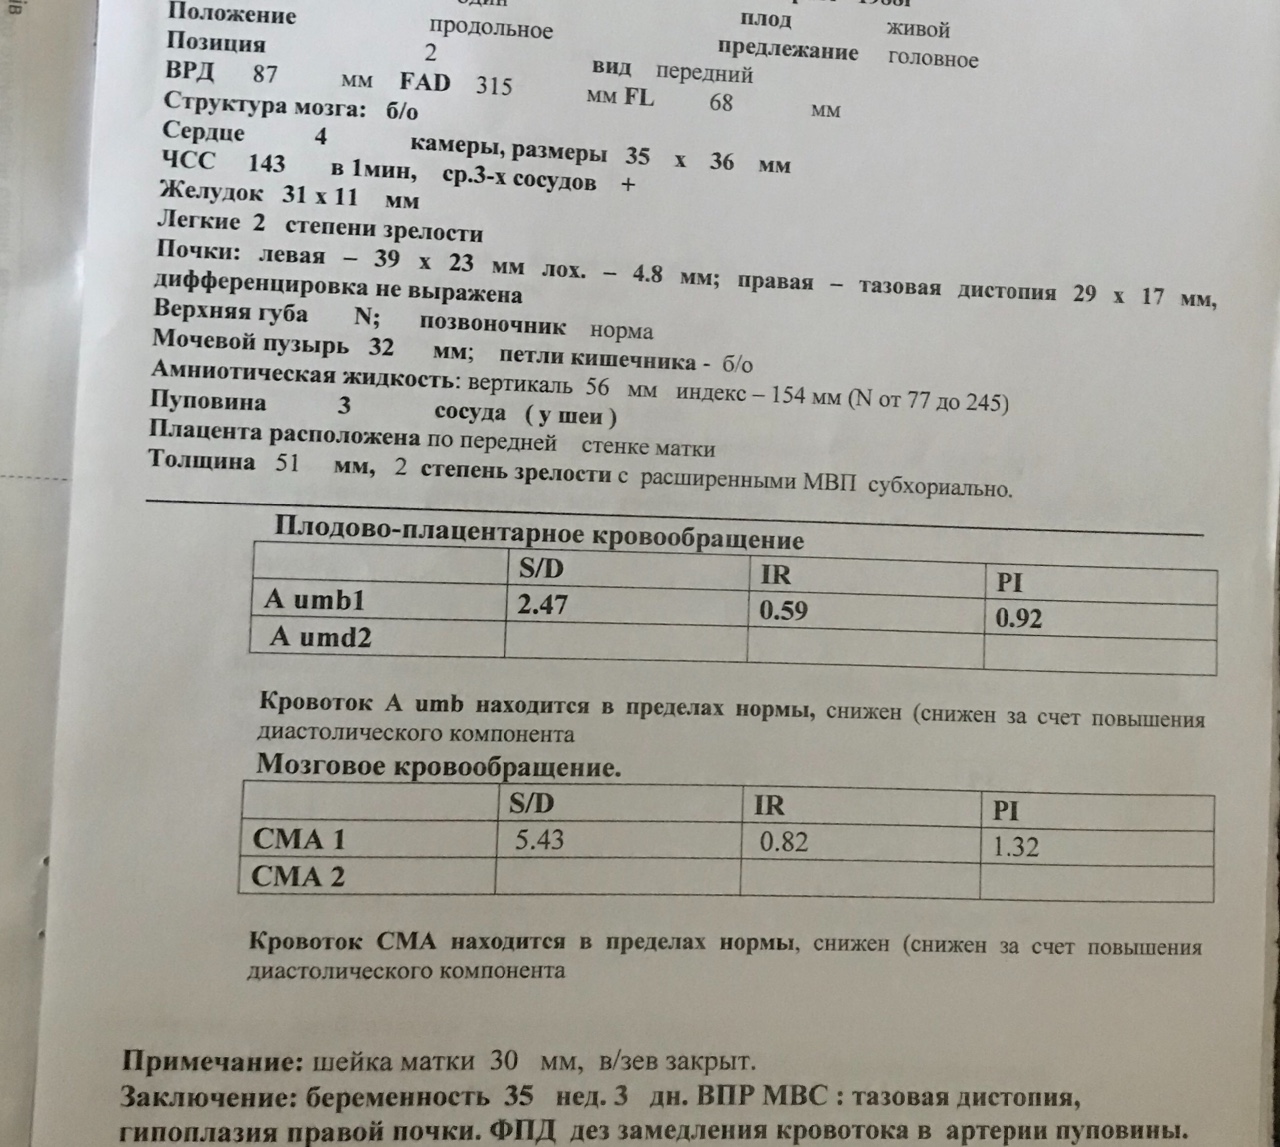

УЗИ на 35 неделе доплер норма

Норма ИАЖ В 35 недель беременности